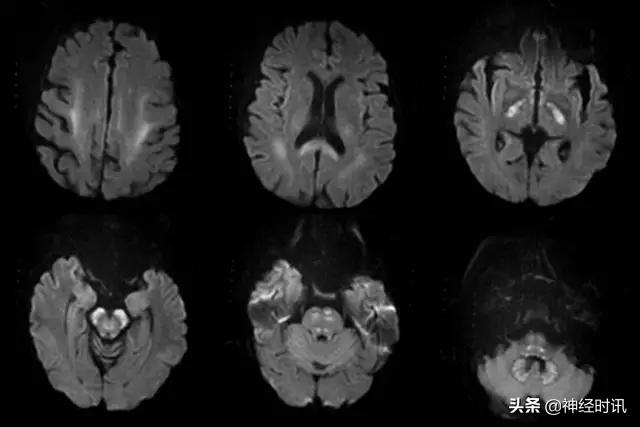

图1 脑卒中及其类似疾病的主要影像表现类型